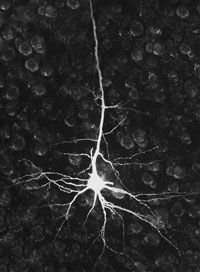

Так, центральная нервная система морского зайца состоит всего из 20 тысяч нервных клеток, причем некоторые из них можно увидеть невооруженным глазом (для сравнения, головной мозг человека содержит около 100 млрд. нейронов, каждый из которых в среднем образует 10 тысяч синапсов с другими нейронами).